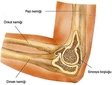

Dirsek İçindeki Ağrının Olası Nedenleri

Dirsek bölgesindeki ağrının nedenleri şunlardır:

• Tendonit: Dirsekteki tendonların iltihaplanması durumudur. Özellikle tenis oynayan kişilerde görülen "tenisçi dirseği" (lateral epikondilit) ve "golfçü dirseği" (medial epikondilit) bu duruma örnektir.

• Burzit: Dirseğin etrafındaki bursaların iltihaplanmasıdır. Bu durum genellikle aşırı kullanıma bağlı olarak ortaya çıkar.

• Artrit: Romatoid artrit veya osteoartrit gibi eklem iltihapları, dirsek ağrısına neden olabilir.

• Sinir Sıkışması: Ulnar sinir sıkışması, dirseğin iç kısmında ağrı ve uyuşma hissine neden olabilir.

• Kırık veya Çatlak: Dirsek bölgesinde meydana gelen bir kırık veya çatlak, ciddi ağrıya yol açabilir.

• Damar Problemleri: Dirsekteki kan damarlarının daralması veya tıkanması, ağrıya neden olabilir.